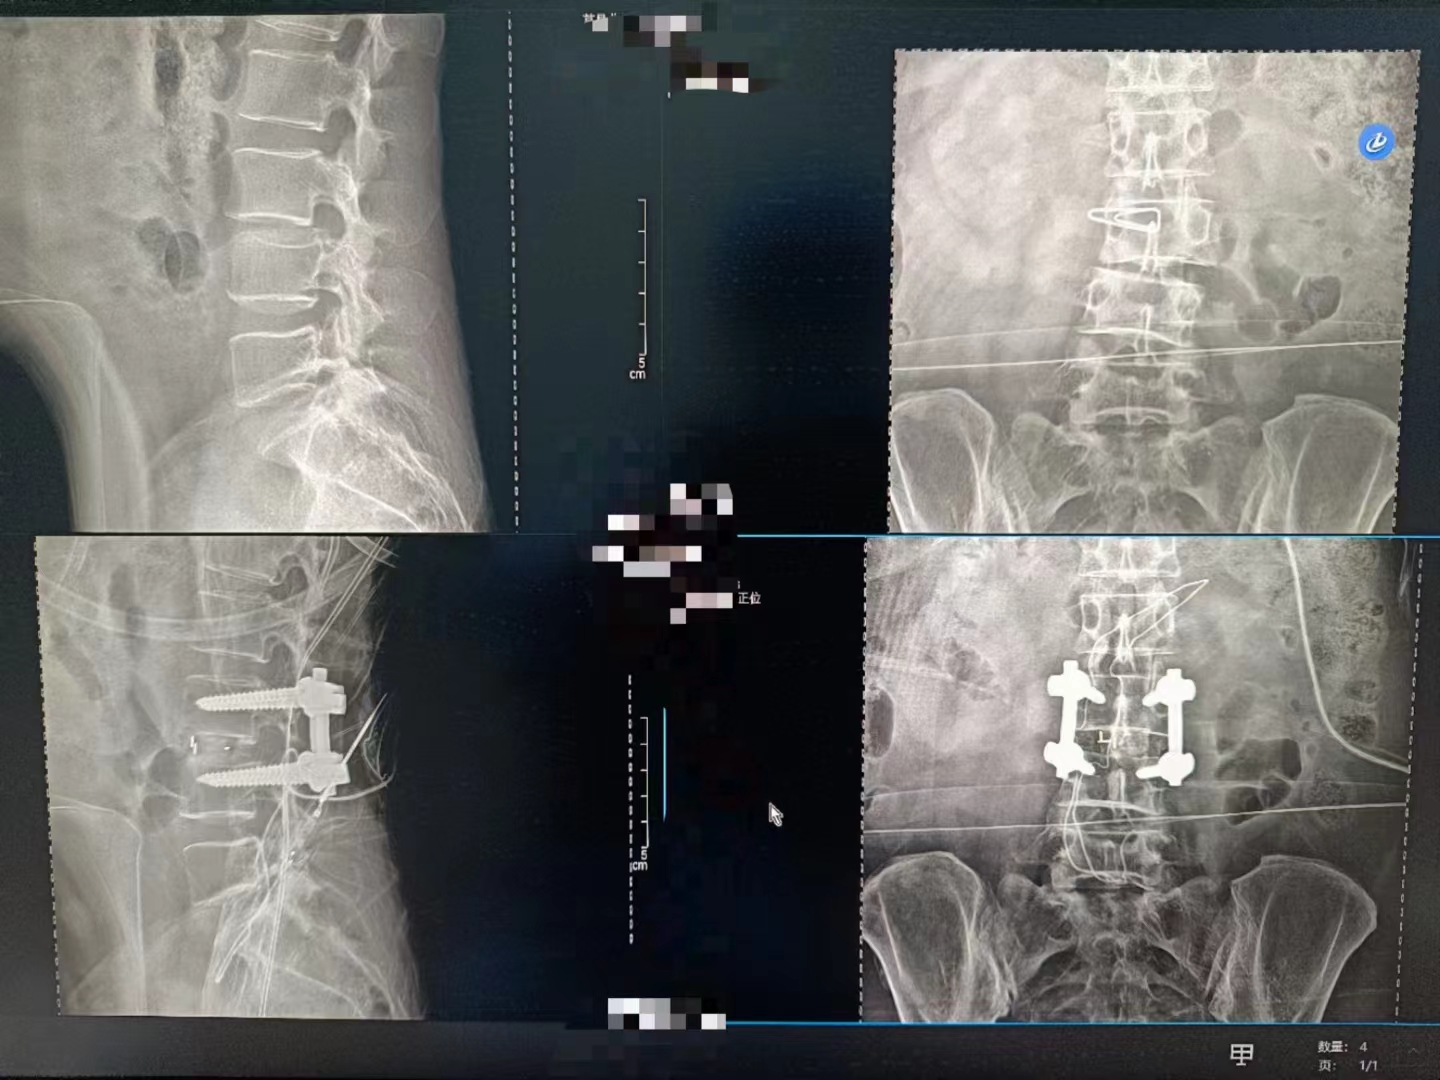

當(dāng)設(shè)備啟動,那束柔和的X射線穿過患者的身體,捕捉下每一個細(xì)微的影像。那一刻,時間仿佛凝固,所有的目光都聚焦在那塊屏幕上。那里,生命的紋理清晰可見,疾病的陰影無處遁形。

手術(shù)順利完成,當(dāng)醫(yī)生們露出疲憊而欣慰的笑容時,我知道,那不僅僅是勝利的喜悅,更是對生命的敬畏與珍視。而這一切,都離不開這臺數(shù)字化X射線攝影設(shè)備的默默付出。